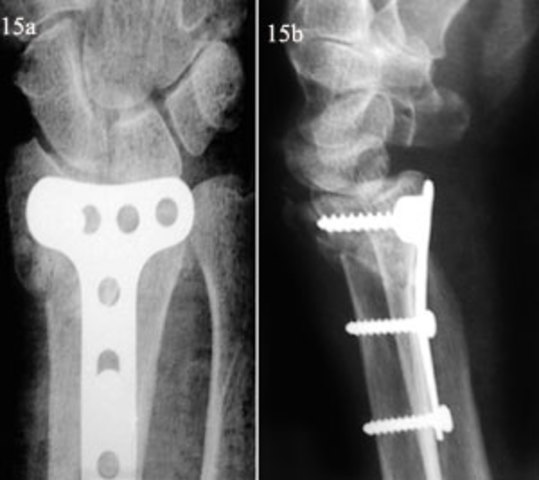

Se usan placas de acero para el auxilio en la reparación de fracturas de huesos.

Se emplean tornillos de carbón para placas de fijación en ruptura de huesos. Estos fueron desarrollados por W.A. Lane

Se implantan las primeras placas oseas de metal con el objetivo de separar roturas o fracturas.

Se implementa el uso de acero inoxidable debido a su resistencia a la corrosión y la maleabilidad como dispositivo ortopédico.